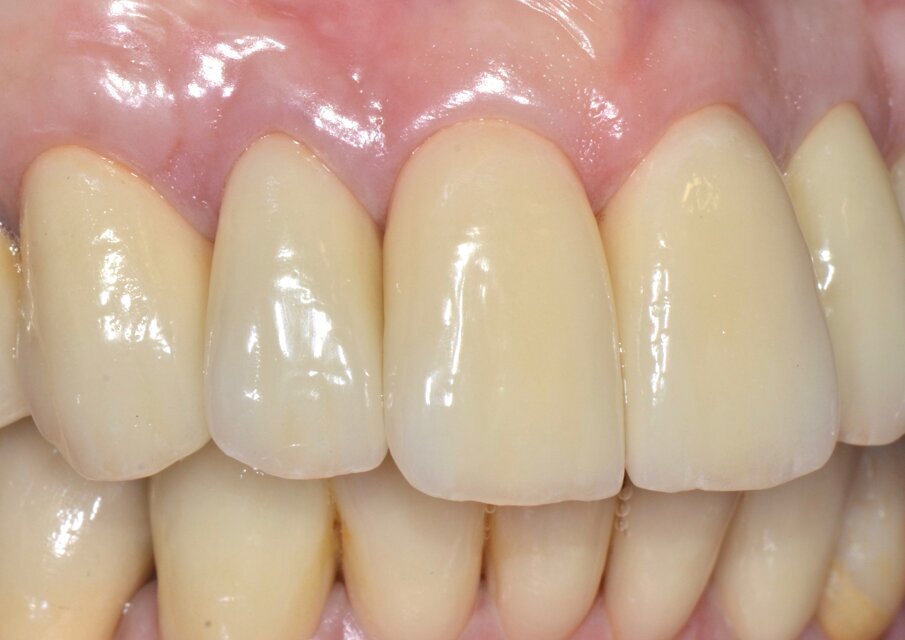

Valutiamo di aver raggiunto una buona simmetria delle parabole gengivali per cui si può procedere con la finalizzazione protesica (Fig. 20). I monconi sono stati preparati con una preparazione verticale per dare priorità alla robustezza dei monconi stessi nella zona cervicale (Figg. 21, 22).

Dal momento che si tratta di un caso estetico senza coinvolgimento parodontale la preparazione è stata molto delicata nei confronti dei tessuti con un posizionamento previsto delle corone definitive leggermente intrasulculare. Una buona conoscenza della fisiopatologia del parodonto unita ad una ottimale gestione degli aspetti protesici dimostra che con ogni tipo di finishing-line si possono ottenere risultati estetici soddisfacenti, ben sapendo peraltro che l’estetica dei manufatti protesici dipende soprattutto dalla bravura e dal senso artistico dei nostri odontotecnici.

La successiva prova clinica è quella delle ceramiche a biscotto durante la quale viene valutata l’occlusione, la fonetica e l’estetica (Figg. 30-33). Durante la stessa seduta viene eseguita la preparazione per la faccetta in disilicato di litio per il canino superiore sinistro che viene rilevata insieme con l’impronta di rimontaggio delle corone superiori. Una faccetta in resina sul canino viene ribasata e solidarizzata al provvisorio superiore (Figg. 34). La settimana successiva i manufatti finiti vengono provati, cementati adesivamente e vengono eseguite le radiografie finali di controllo (Figg. 35-47).